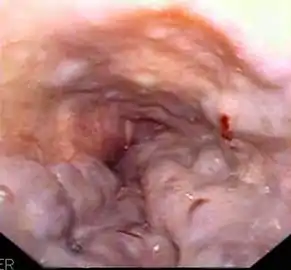

Полипы фундальных желёз желудка. Изображение получено с помощью фиброгастроскопа